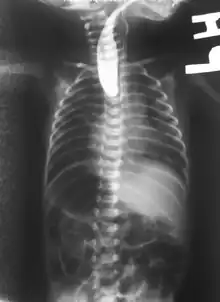

On plain X-ray, a feeding tube will not be seen pass through the esophagus and remain coiled in the upper oesophageal pouch.[8]

If any of the above signs/symptoms are noticed, a catheter is gently passed into the esophagus to check for resistance. If resistance is noted, other studies will be done to confirm the diagnosis. A catheter can be inserted and will show up as white on a regular x-ray film to demonstrate the blind pouch ending. Sometimes a small amount of barium (chalk-like liquid) is placed through the mouth to diagnose the problems. However, performing such an oral contrast study is not advised due to a risk of aspiration.[27]